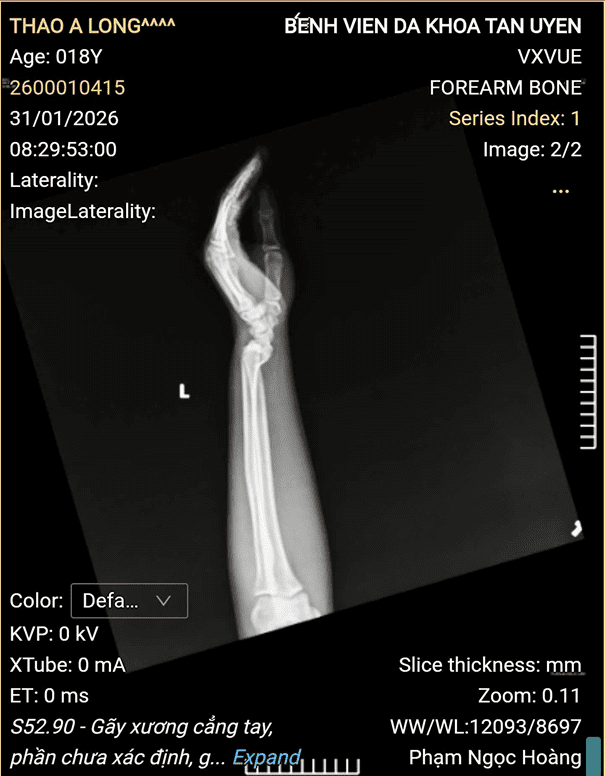

Khi vào viện, bệnh nhân trong tình trạng đau nhiều, hạn chế vận động cẳng tay hai bên, kèm theo xây xát da vùng mặt. Ngay sau khi tiếp nhận, bệnh nhân được các bác sĩ, điều dưỡng Khoa Ngoại phối hợp với các khoa liên quan khẩn trương thăm khám, chụp X-quang và làm các xét nghiệm cần thiết. Kết quả chẩn đoán xác định bệnh nhân bị gãy đầu dưới xương quay hai bên.

Hình ảnh của bệnh nhân và Bác sĩ Khoa Ngoại:

Hình ảnh của bệnh nhân trước khi kéo nắn.